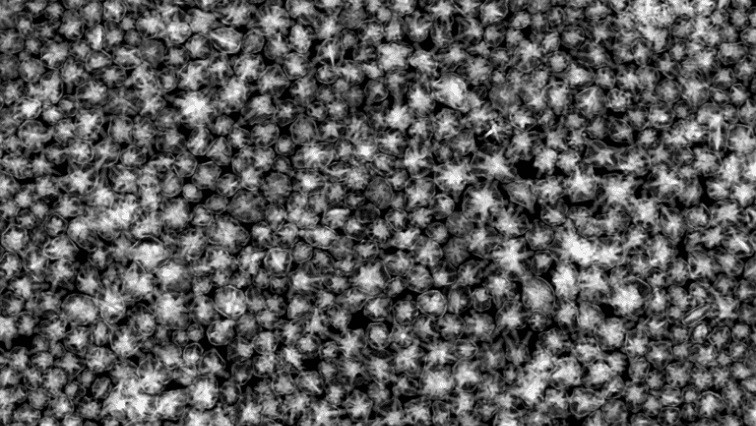

In the quest for non-invasive cancer therapies, light-based treatments like nanoparticle-mediated photothermal therapy (PTT) have emerged as promising candidates. During these therapies, nanoparticles, often shaped like rods or tiny stars, are injected into the body and travel via the circulatory system before accumulating in cancerous tumors. Once enough nanoparticles saturate the tumor, lasers are used to heat up the particles, which can then destroy the surrounding cancerous cells. Nanoparticle-based PTT has even recently been used to successfully treat prostate cancer in humans, and additional clinical trials are ongoing.

Canning and Vu tested the efficacy of their system in a mouse model for bladder cancer using an updated version of the gold nanostars. Canning’s new design encases each nanostar within a hollow gold shell that stabilizes the star’s branches as they heat, preventing them from melting into spheres. When coupled with Vu’s PACT system, the team was easily able to detect and image the nanostars and monitor the progress of the photothermal treatment. By more precisely monitoring the temperature, the team was able to observe the ideal temperature dosage needed to activate the nanostars and destroy cells.